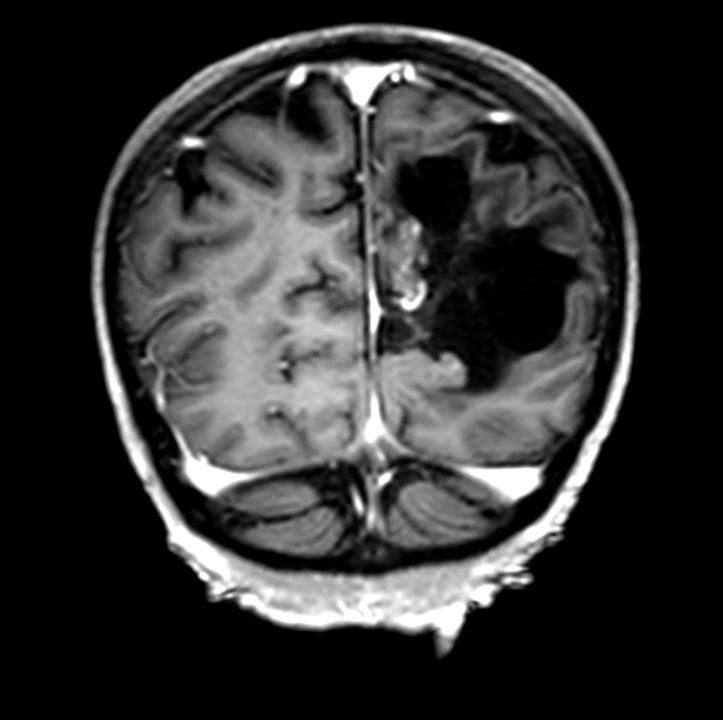

3D VIEW - T2w FLAIR (axial reformat)